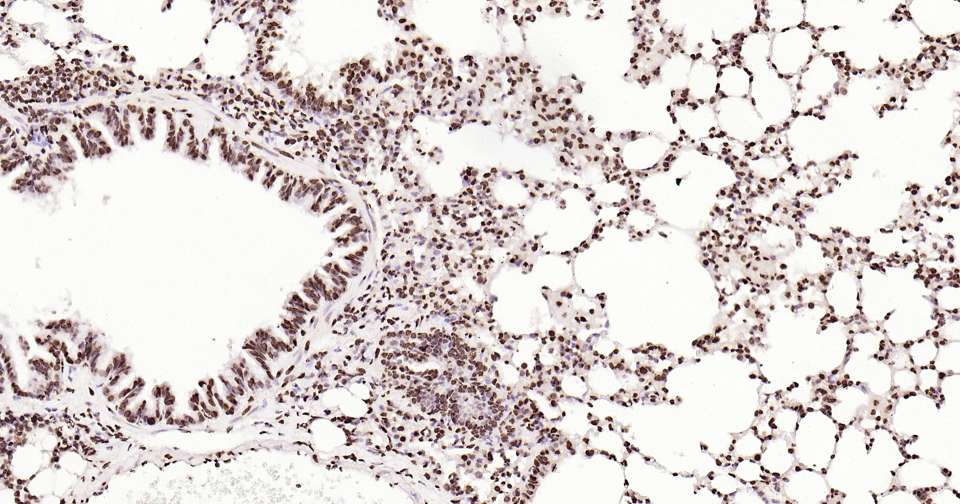

Immunohistochemical analysis of paraffin embedded mouse lung tissue slide using IHC0308M (Mouse Histone H2A.X Kit).